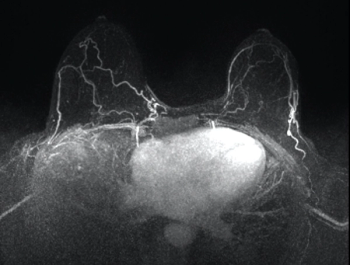

Concerns have been raised about the safety of GBCA. Experts review the latest data to support counseling of patients who may have repeated exposure.